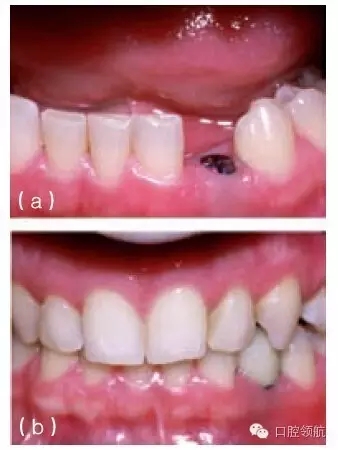

在可視性較高的無牙區(qū)植入種植體時,要想獲得理想的軟組織外形和鄰間牙齦乳頭高度是一個挑戰(zhàn)??赡艽嬖诟鞣N各樣的問題:牙與牙之間黑三角間隙的存在(圖10.22a,b);邊緣組織的厚度大于鄰牙牙齦邊緣厚度(圖10.23);與相鄰或對側的天然牙相比,軟組織邊緣的根向位置可能不在同一高度上(圖10.24);牙齦乳頭可能不具備最理想的外形或高度(圖10.21~圖10.25);由于軟組織退縮造成臨床牙冠長度改變或金屬暴露(圖10.26a,b)。

圖10.22 (a)金屬烤瓷冠的唇側觀,可見近中觸點下方一較小的黑色間隙,如果有齦乳頭的充填這些間隙就看不到。(b)種植體植入到尖牙區(qū),該區(qū)可見到明顯的牙槽嵴吸收和牙齦萎縮。在種植體冠的頸部可見到相對較大的黑色間隙。